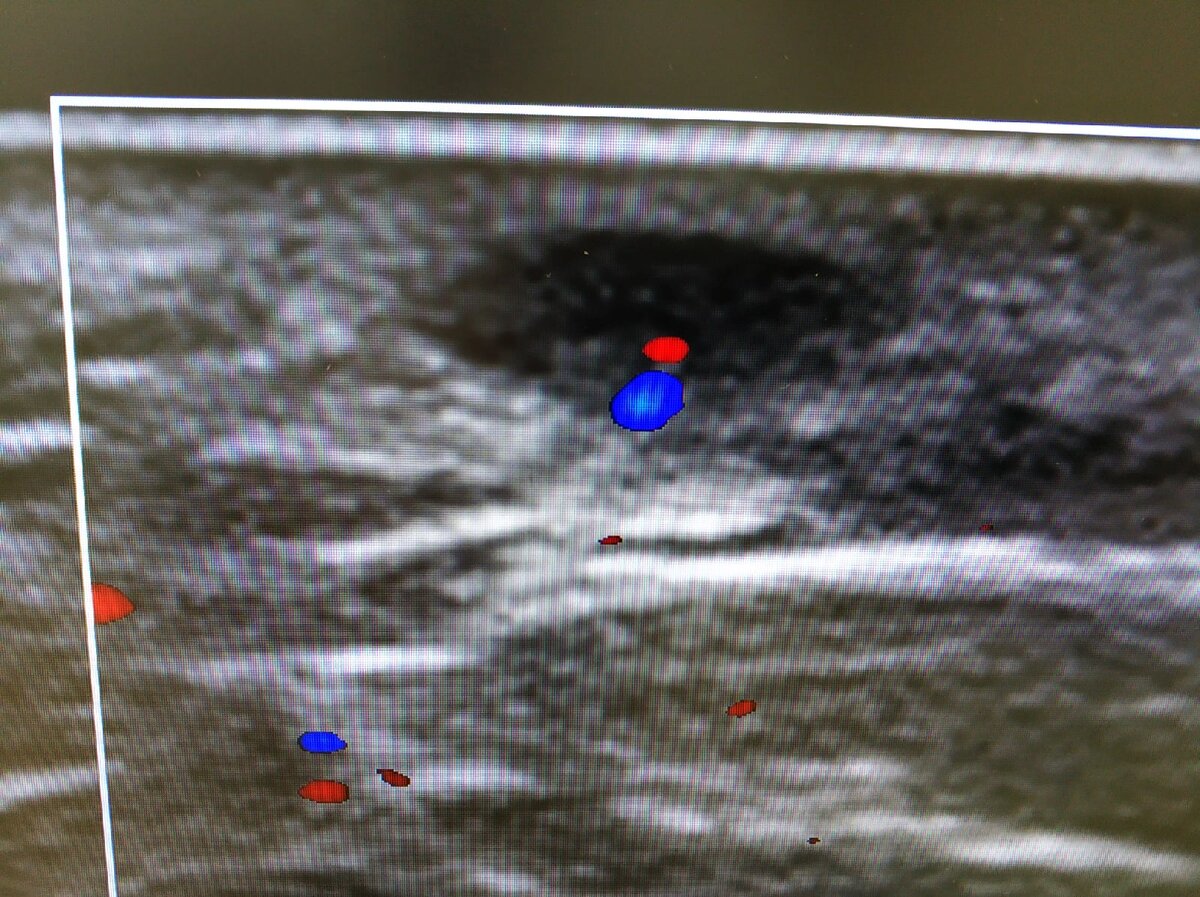

🧐Пальпируемое образование промежности в виде маленького шарика. Пациент направлен для исключения связи с прямой кишкой, а так же разобраться с природой образования.

🖼️На снимке образование овальной формы, горизонтально ориентировано, преимущественно гипоэхогенное. Расположено в дерме, немного выходит в гиподерму.

👨‍💻При снижении динамического диапазона виден гиперэхогенный компонент с единичным сосудом. Сосуд входит через одну точку, гиперэхогенный тяж к краю образования - ворота. Структура типичная для лимфоузлов.